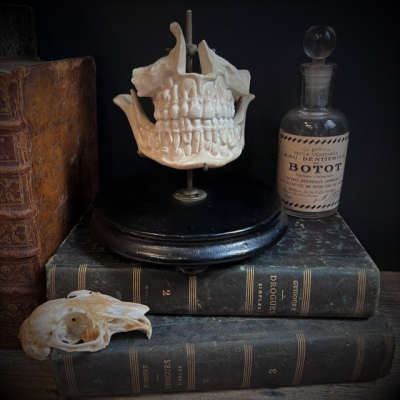

Human jaws in porcelain mounted on a blackened wooden base

Anatomical dental model for dentists

19th century

Human jaws in porcelain mounted on a blackened wooden base - Napoleon III type

Anatomical dental model for dentists of the lower skull from the 19th century

There is a small lack at the nasal level, when viewed from the front on the right side.

I had never seen an anatomical model in porcelain before.

Model for dental surgeon or stomatologist?

Nice piece

What is original is that the whole piece is made of unglazed porcelain, which is called biscuit, except for the teeth which are well glazed.

Diameter of the base: 15cm

Total height: 15/16cm

Original metal fixation system